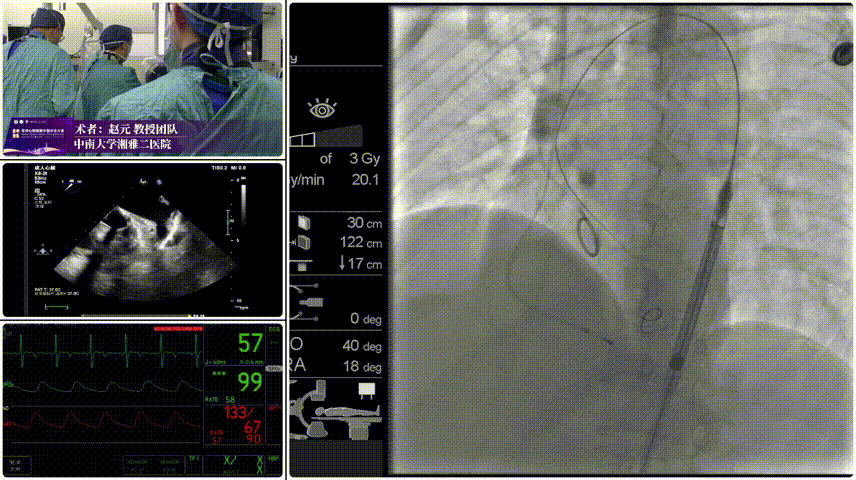

手术过程

Step 1.柔顺过弓:精湛手术操作+优异通过性能、复杂弓形无任何辅助一次通过。

Step 2.定位释放:初始高定位,使瓣膜自然下滑至理想位置。

Step 3.工作位评估:位置合适,深放以避免瓣膜开合区过度受挤压。

Step 4.稳定脱钩无位移。

Step 5.最终造影:位置合适,瓣膜形态良好,无瓣周漏。

患者压差由105mmHg降至17mmHg。

手术过程与术后转归